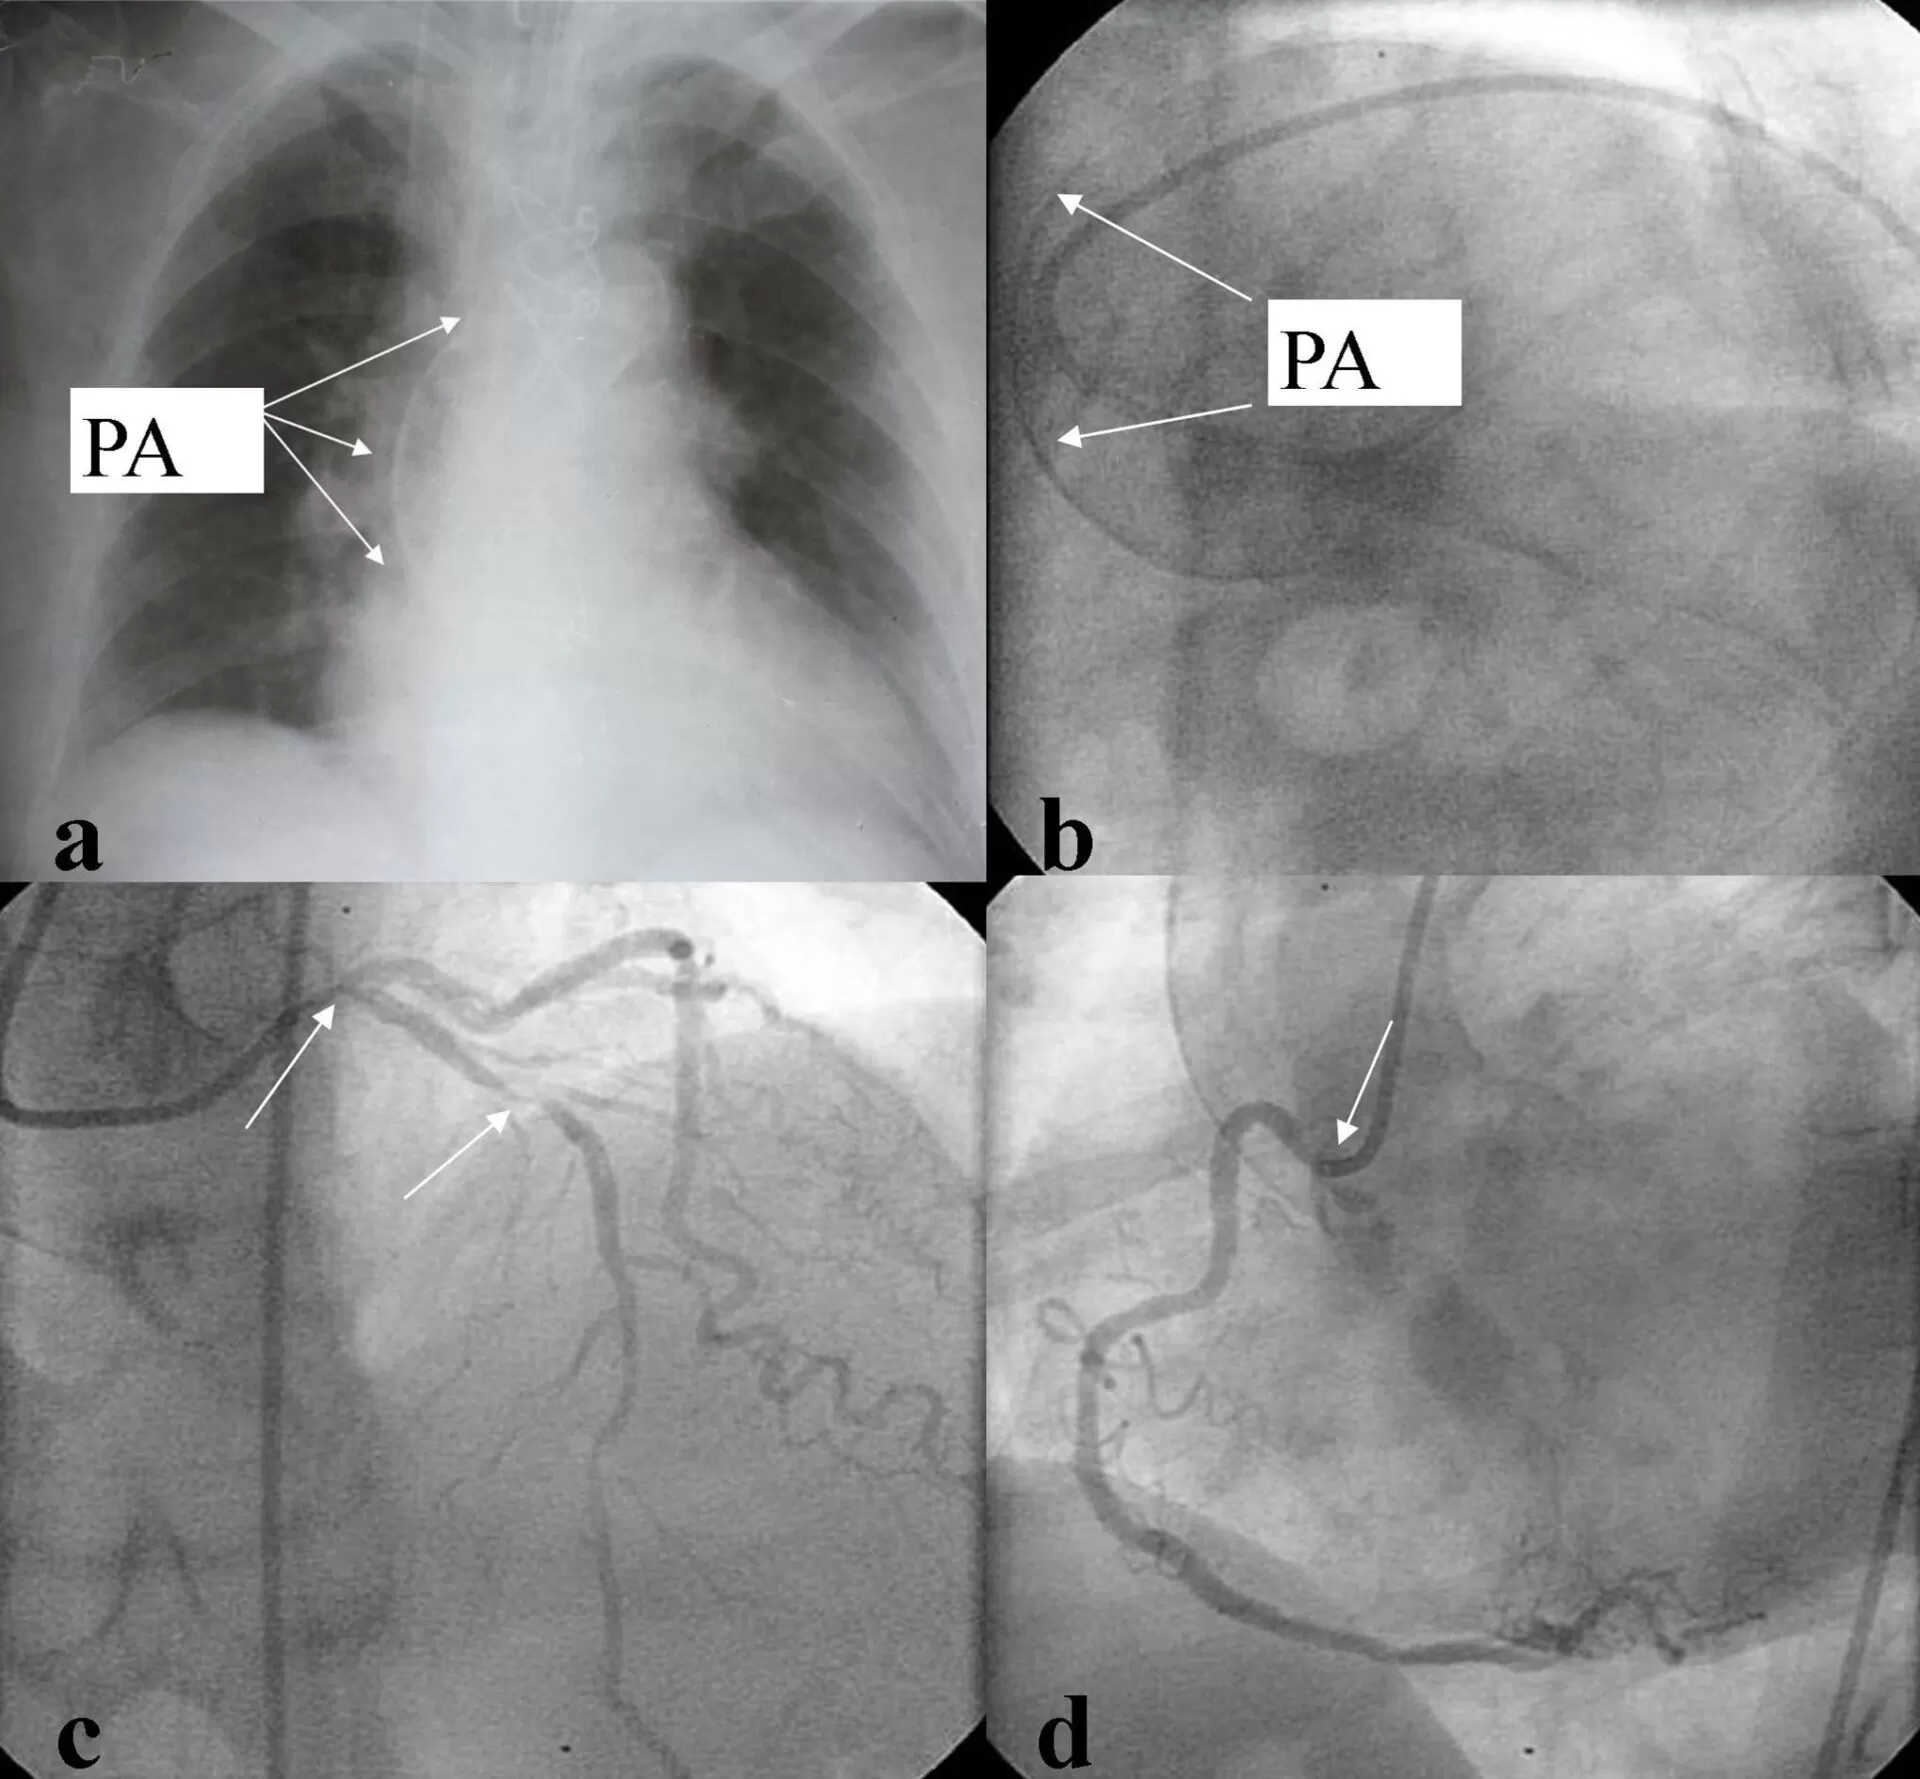

We present a 64-year-old woman was admitted with progressive angina, Canadian Cardiovascular Society Class III at admission, not relieved by optimal medical therapy. Antecedents of arterial hypertension, diabetes, and hypercholesterolemia as risk factors for coronary artery disease were present. Preoperative chest X-ray (fig. 1a) showed severe ascending aortic calcification, which was also visible during cardiac catheterization (Fig. 1b). Significant left main coronary artery stenosis and significant proximal lesions of the left anterior descending artery (LDA), left circumflex artery, and the right coronary artery (Fig. 1c y d) demanded surgical revascularization.

Figure 1: Porcelain aorta and significant left main coronary artery stenosis plus severe three vessel diseases

a: chest X-ray.

b: Cardiac catheterization.

c: Significant left main coronary artery stenosis.

d: Significant lesions in right coronary artery.